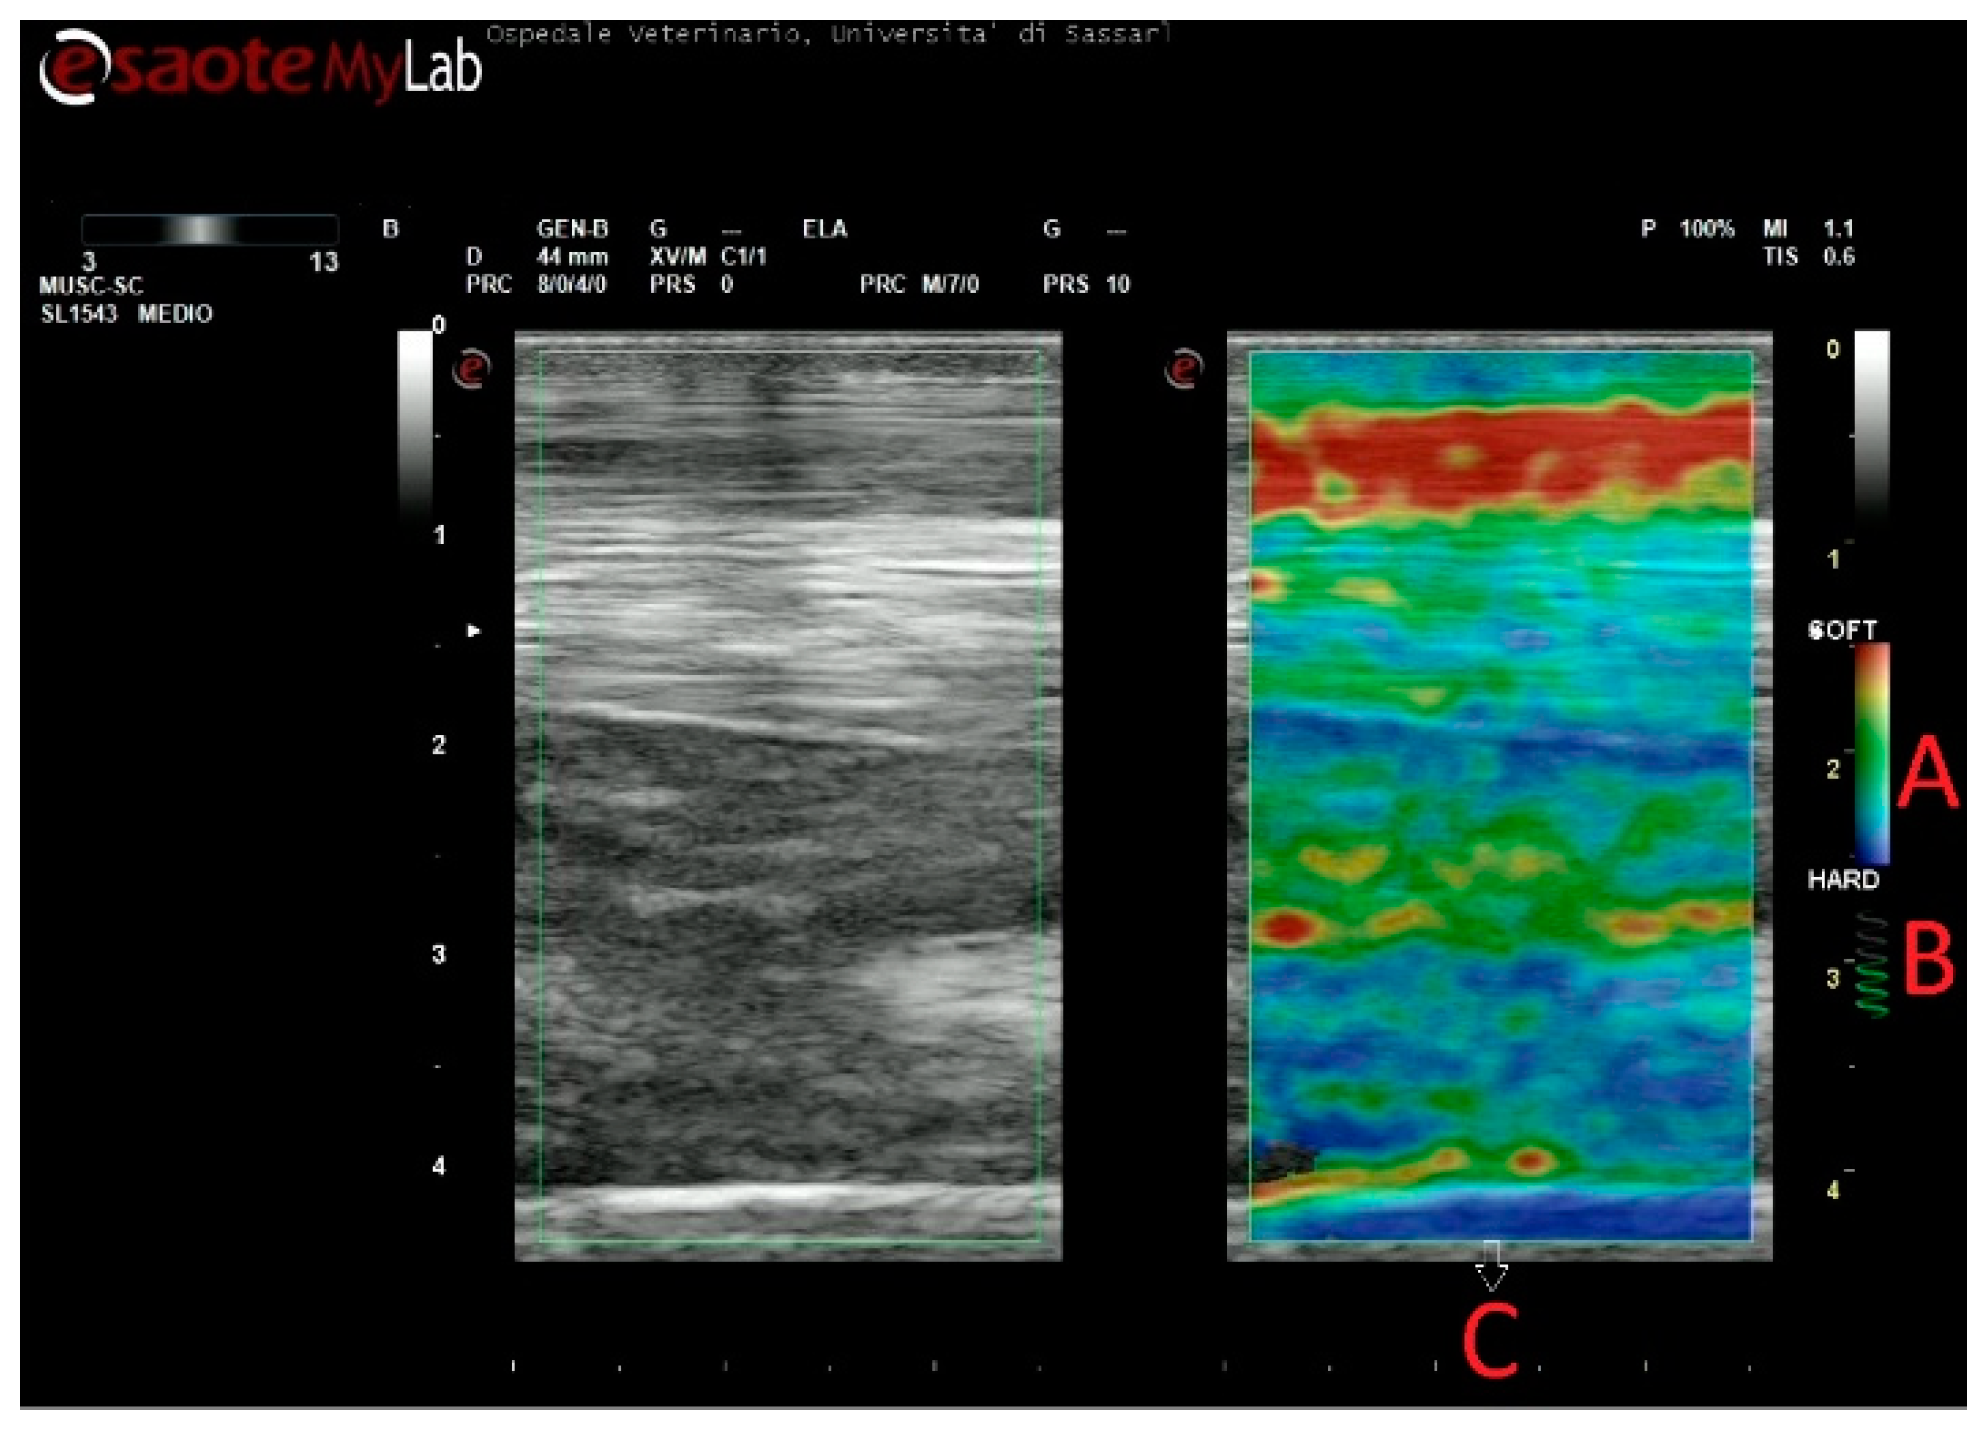

The SE images were obtained without a standoff pad, which can be problematic for a correct evaluation of the elasticity pattern. The lack of accurate contact between the probe and standoff pad can produce reverberation artifacts, which are visible as parallel red areas in the elastogram, which can be confused with areas of softness [6,42]. In addition, the inclusion of the pad in the Fov can alter the color pattern of SE-derived elastograms, because of its well-known relativity. The standoff pad can represent the softest part within the elastographic window, and, as a consequence, SDFT lesions can be misinterpreted or underestimated, no longer appearing as red but yellow/green—in other words, with intermediate stiffness. Finally, the use of the pad can alter the elasticity estimation since the deepest structures, which we decided to include (suspensory ligament and cannon bone), are probably more difficult to reach. This can subsequently lead to a lack of signal, without any color (Figure 7).

Figure 7. At the bottom of the field of view (Fov), an artifact is present as a lack of signal, without any colors. This could be explained by the use of the pad, as the deepest structures, where the artifact appears, are probably more difficult to reach, compared with images obtained without a pad. Secondly, the inclusion of a standoff pad within Fov can alter the color pattern of strain elastography-derived elastograms, because of its relativity; the standoff pad can represent the softest part within elastographic window, and as a consequence, the superficial digital flexor tendon lesions can be misinterpreted or underestimated, no longer appearing red but yellow/green.